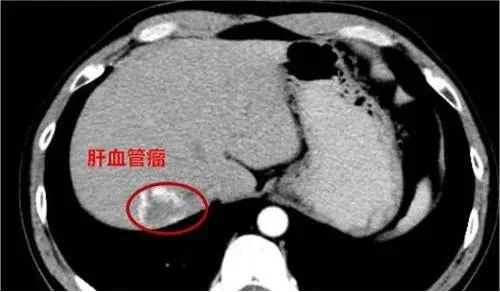

通过B超,部分位于深部肌肉或器官内的血管瘤可以被及时发现,例如:

长在肝脏内的血管瘤,可能压迫肝内胆管,导致胆汁排泄不畅,引起黄疸;